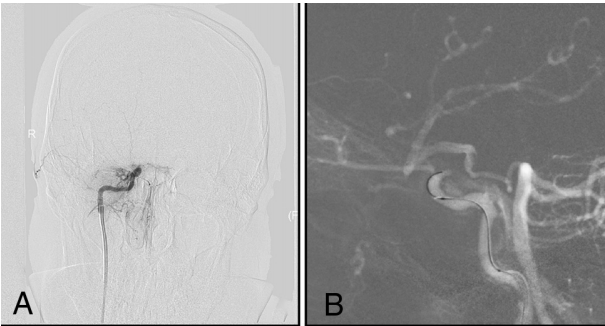

对于典型明显存在PcomA或AcomA的I型和II型病变,我们使用了双侧血管同时注入造影剂建立路图明确阻塞节段(图2和3)。微导丝(Synchro,Stryker;Transend EX 014/205软头,Stryker)与微导管(Echelon-10,Medtronic;Excelsior SL-10,Stryker)结合使用,小心地通过闭塞节段。如果反复尝试,微导丝和微导管不能通过闭塞节段进入远端血管真腔,则停止手术。如果成功引导微导丝穿过闭塞节段,则微导管造影确认微导管在闭塞远端血管真腔内。随后,将长交换微导丝(Transend ES 014/300 Floppy;Stryker)放置在适当的位置锚定,收回微导管。沿微导丝送入2-2.5mm的Gateway(Stryker)球囊至闭塞节段球扩成形。根据球囊扩张后闭塞血管近端和远端的直径以及长度,根据术者的熟悉度释放自膨支架(Wingspan,Stryker;Neuroform EZ,Stryker;或Enterprise,Codman&Shurtleff)。

图2. 男性患者,左侧肢体无力15天。A,DSA显示右侧颈内动脉颅内段闭塞,闭塞长度为≤10mm,通过PcomA(I型)向ICA颅内远端代偿供血;B和C,在双路图的指导下,微导丝与微导管的结合穿过了闭塞节段;D,成功再通。